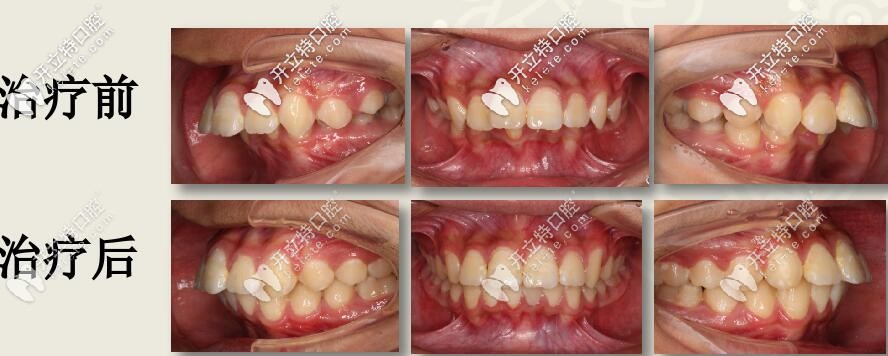

肉眼可見(jiàn)上前牙唇傾,輕度擁擠 下頜牙弓寬度窄,前牙區(qū)擁擠,后牙去舌傾明顯,前牙深覆蓋,深覆合

I期II期聯(lián)合矯治

1、I期:口外弓抑制上頜發(fā)育,肌激動(dòng)器促進(jìn)下頜發(fā)育

2、II期:全口直絲弓非拔牙矯治,排齊整平上下牙列

3、四眼簧改善下后牙舌傾異常,擴(kuò)弓提供排齊間隙

4、斜導(dǎo)導(dǎo)下頜向前,維持I期前移效果

5、改善面型、改善咬合關(guān)系

矯治時(shí)間:27個(gè)月

結(jié)束后,牙列整齊,深復(fù)蓋明顯改善。

本案例,用到了口外弓、肌激動(dòng)器、四眼簧擴(kuò)弓、斜導(dǎo)工具